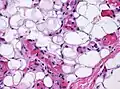

Small vessels in adipose tissue

The vessels typically contain hyaline or fibrin (pictured) thrombi[4]